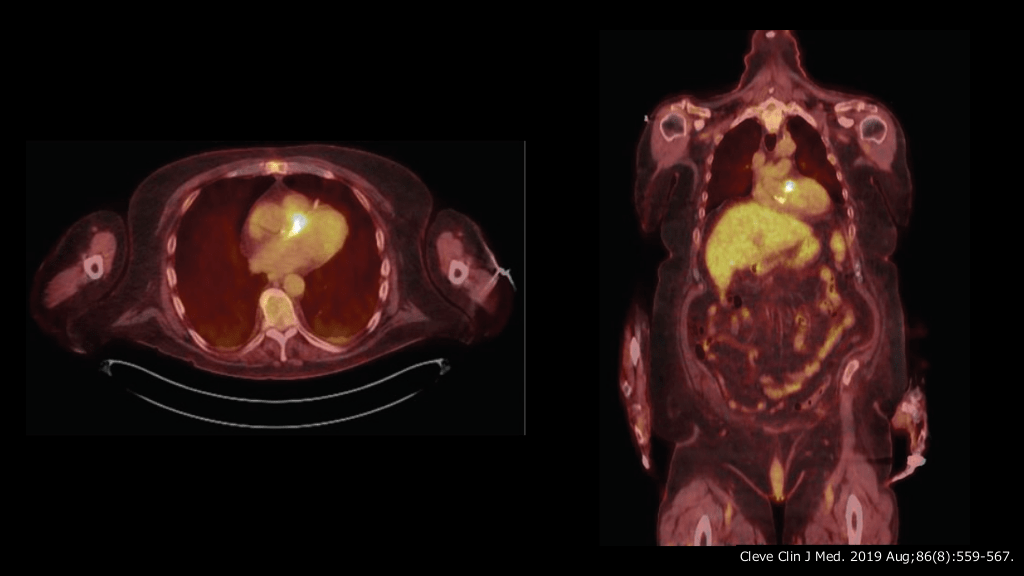

18F-FDG/PET • CT PVEの場合:感度91%, 特異度95% - 術後3ヶ 間は術後変化で集積が認められる場合がある1) • NVEの場合:感度39%, 特異度93%2) • 18FDG - PET/CT撮影の利点として, 脳以外の全 病変検出以外に以下がある3) の末梢性塞栓症と転移性感染症の検出 IEの素因となる潜在病変の診断 (腫瘍性病変) 代替感染源もしくは 感染症の同定 心 非 身 月 1. Cleve Clin J Med. 2019;86(8):559-567. 2. Eur J Nucl Med Mol Imaging 2013; 40(7):1102–1107. 3. Circ Cardiovasc Imaging. 2018;11:e007626.

#59.

Cleve Clin J Med. 2019 Aug;86(8):559-567.